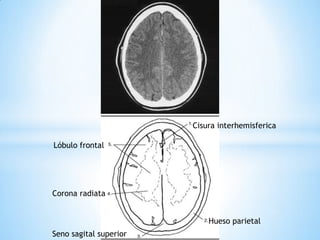

Corona radiata

Hueso parietal

Lóbulo frontal

Cisura interhemisferica

Hoz del cerebro

Hueso frontal

Seno sagital superior Corona radiata Hueso parietal Lóbulo frontal Cisura interhemisferica